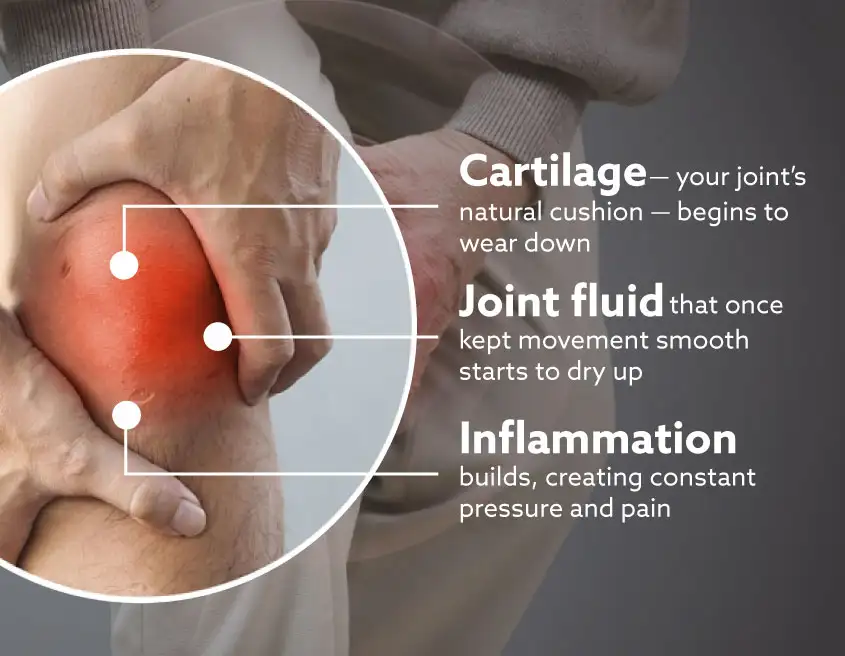

Many people believe knee pain is just an inflammation or its normal as we age.

But here’s the truth: Pain is only the symptom. The real problem is joint degradation, specifically osteoarthritis.

➡️ It starts with the loss of cartilage — the soft cushion and the reduction of joint fluid, which keeps everything moving smoothly.

➡️ Then our two joint bones begin to rub directly against each other. Which only leads to inflammation, soreness, stiffnes,s and eventually pain.